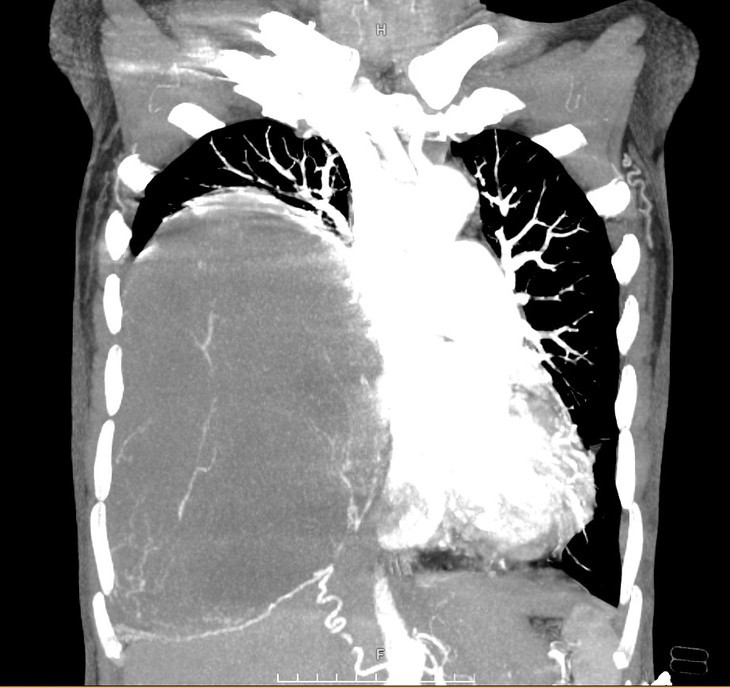

Ca mổ được thực hiện thành công, khối u lấy ra có trọng lượng hơn 2 kg. Trong mổ, bệnh nhân không phải truyền thêm máu dự trù, hồi phục tốt, được rút dẫn lưu màng phổi ngày thứ 3 sau phẫu thuật, ra viện sau 5 ngày. Giải phẫu bệnh sau mổ: u xơ màng phổi đơn độc độ mô học 1.

| Hình ảnh khối u sau khi được phẫu thuật - Ảnh BVCC |